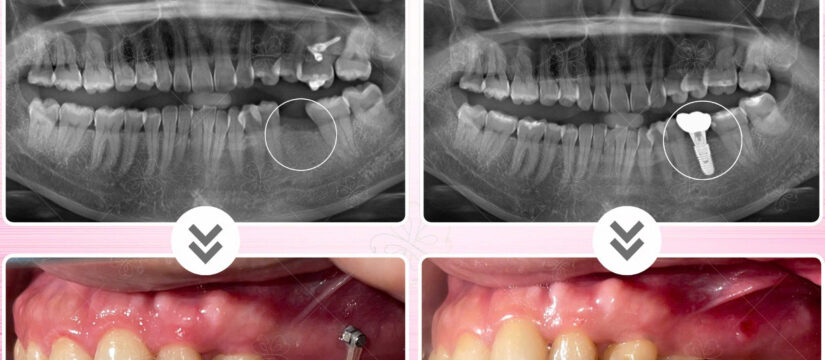

Tiếp tục cập nhật những ca hoàn thiện răng sứ trên implant tại Nha khoa Thiện An BMT Đăk Lăk????

Continue to update cases of finishing porcelain teeth on implants at Thien An Dental Clinic, BMT Dak Lak????